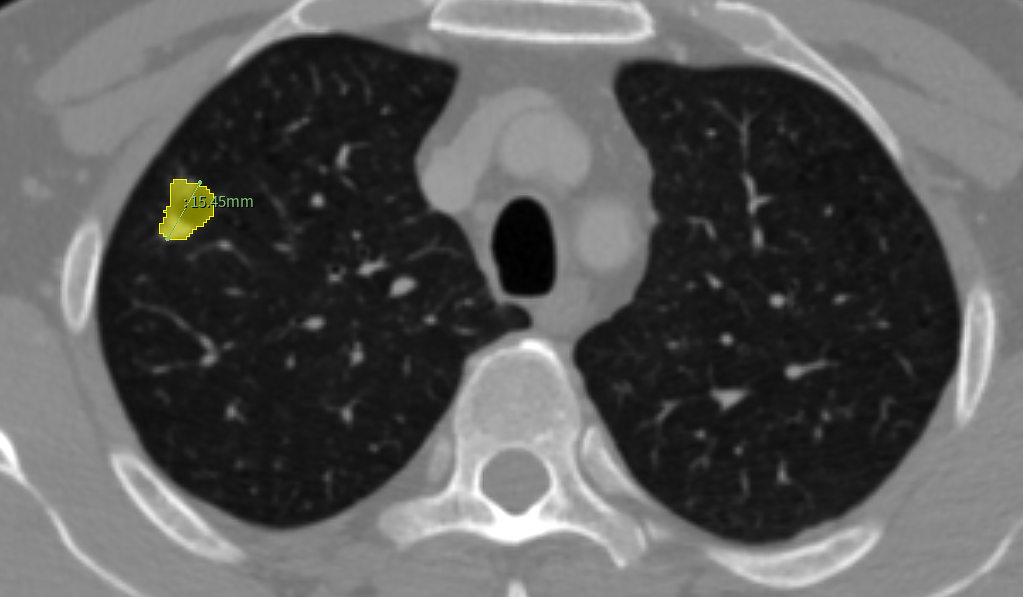

个案分享:术前三维重建的必要性

患者,性别男,CT检查发现右肺上叶前段大小约1.5cmx1.2cm的结节,该患者在术中医生看到后升支动脉和背段动脉在一起,认为是一支动脉,但总感觉不对劲,重新查看了三维重建结果对照发现确实存在动脉变异,从而避免了误断背段动脉的风险

医生感叹:术前三维重建是有用的!

↑CT扫描中,识别出1个结节(约1.5cmx1.2cm)